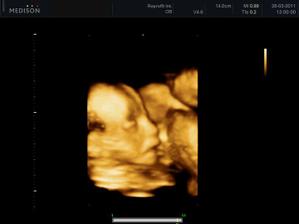

25.3.2011 - 3D utz - tak konečně víme, kdo nám to bydlí v bříšku - je to neuvěřitelný, ale je to malá princezna, hurááá hurááá je to holka - jsme moc šťastní - je to celej táta - i slza ukápla a tátovi taky.A kočenka s panem doktorem opět nespolupracovala, takže maminka opět chodila po chodbě jak trdlo, nakonec se umoudřila a přelehla si na druhej bok, nakonec se nám postavila na hlavu, asi jako už mě nechte být, no byla to sranda - krásný zážitek a nakupujeme růžovou 🙂 - měříme 24 cm a vážíme 320 g